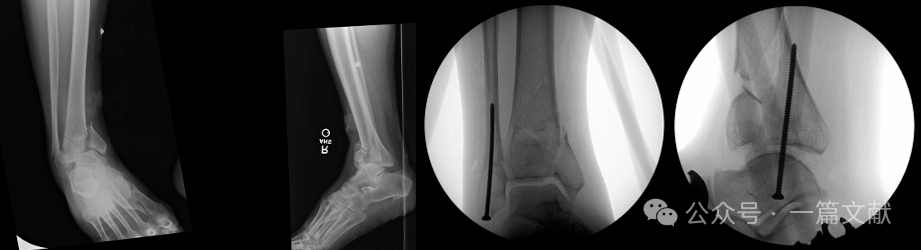

经皮腓骨骨折髓内固定可最大限度保留手术入路选择空间。如下图: